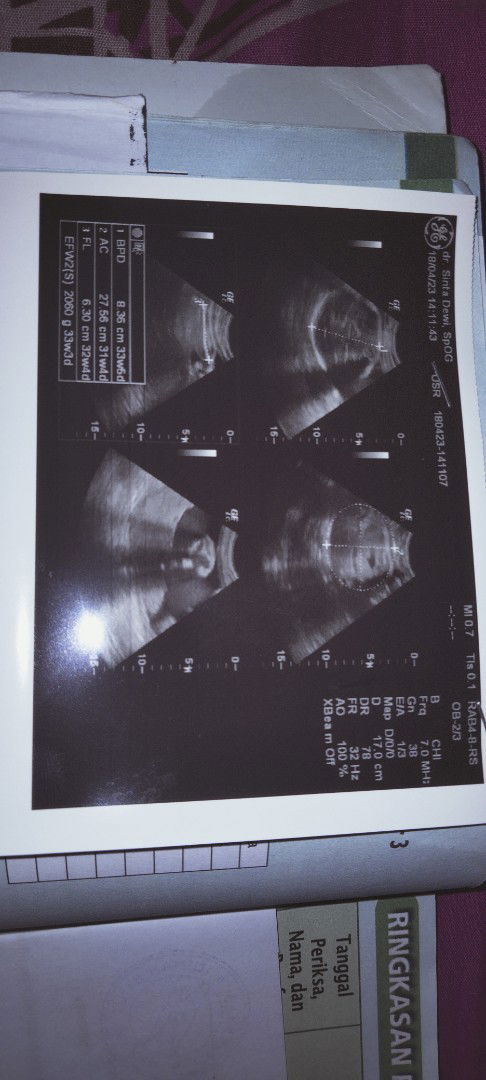

Hasil USG

Hallo bunda, Mau tanya ini hasil USG tadi kata dr. Aku 35w dan BB janin 1.9g Tapi di hasil print di gambar USG beda Bun.. usia kehamilan aku 33w dan BB janin 2060g kira² dari kedua ini mana yang benar ya Bun.. minta pengamatan bunda yg Sudah pengalaman .thanks